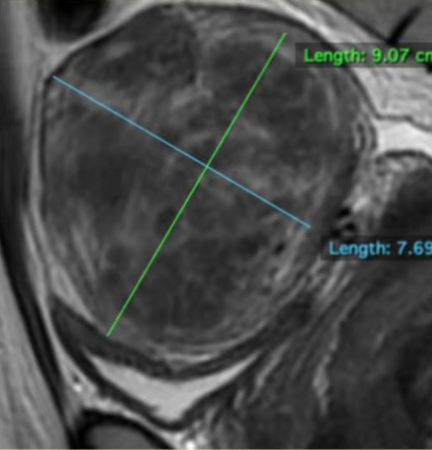

MRI